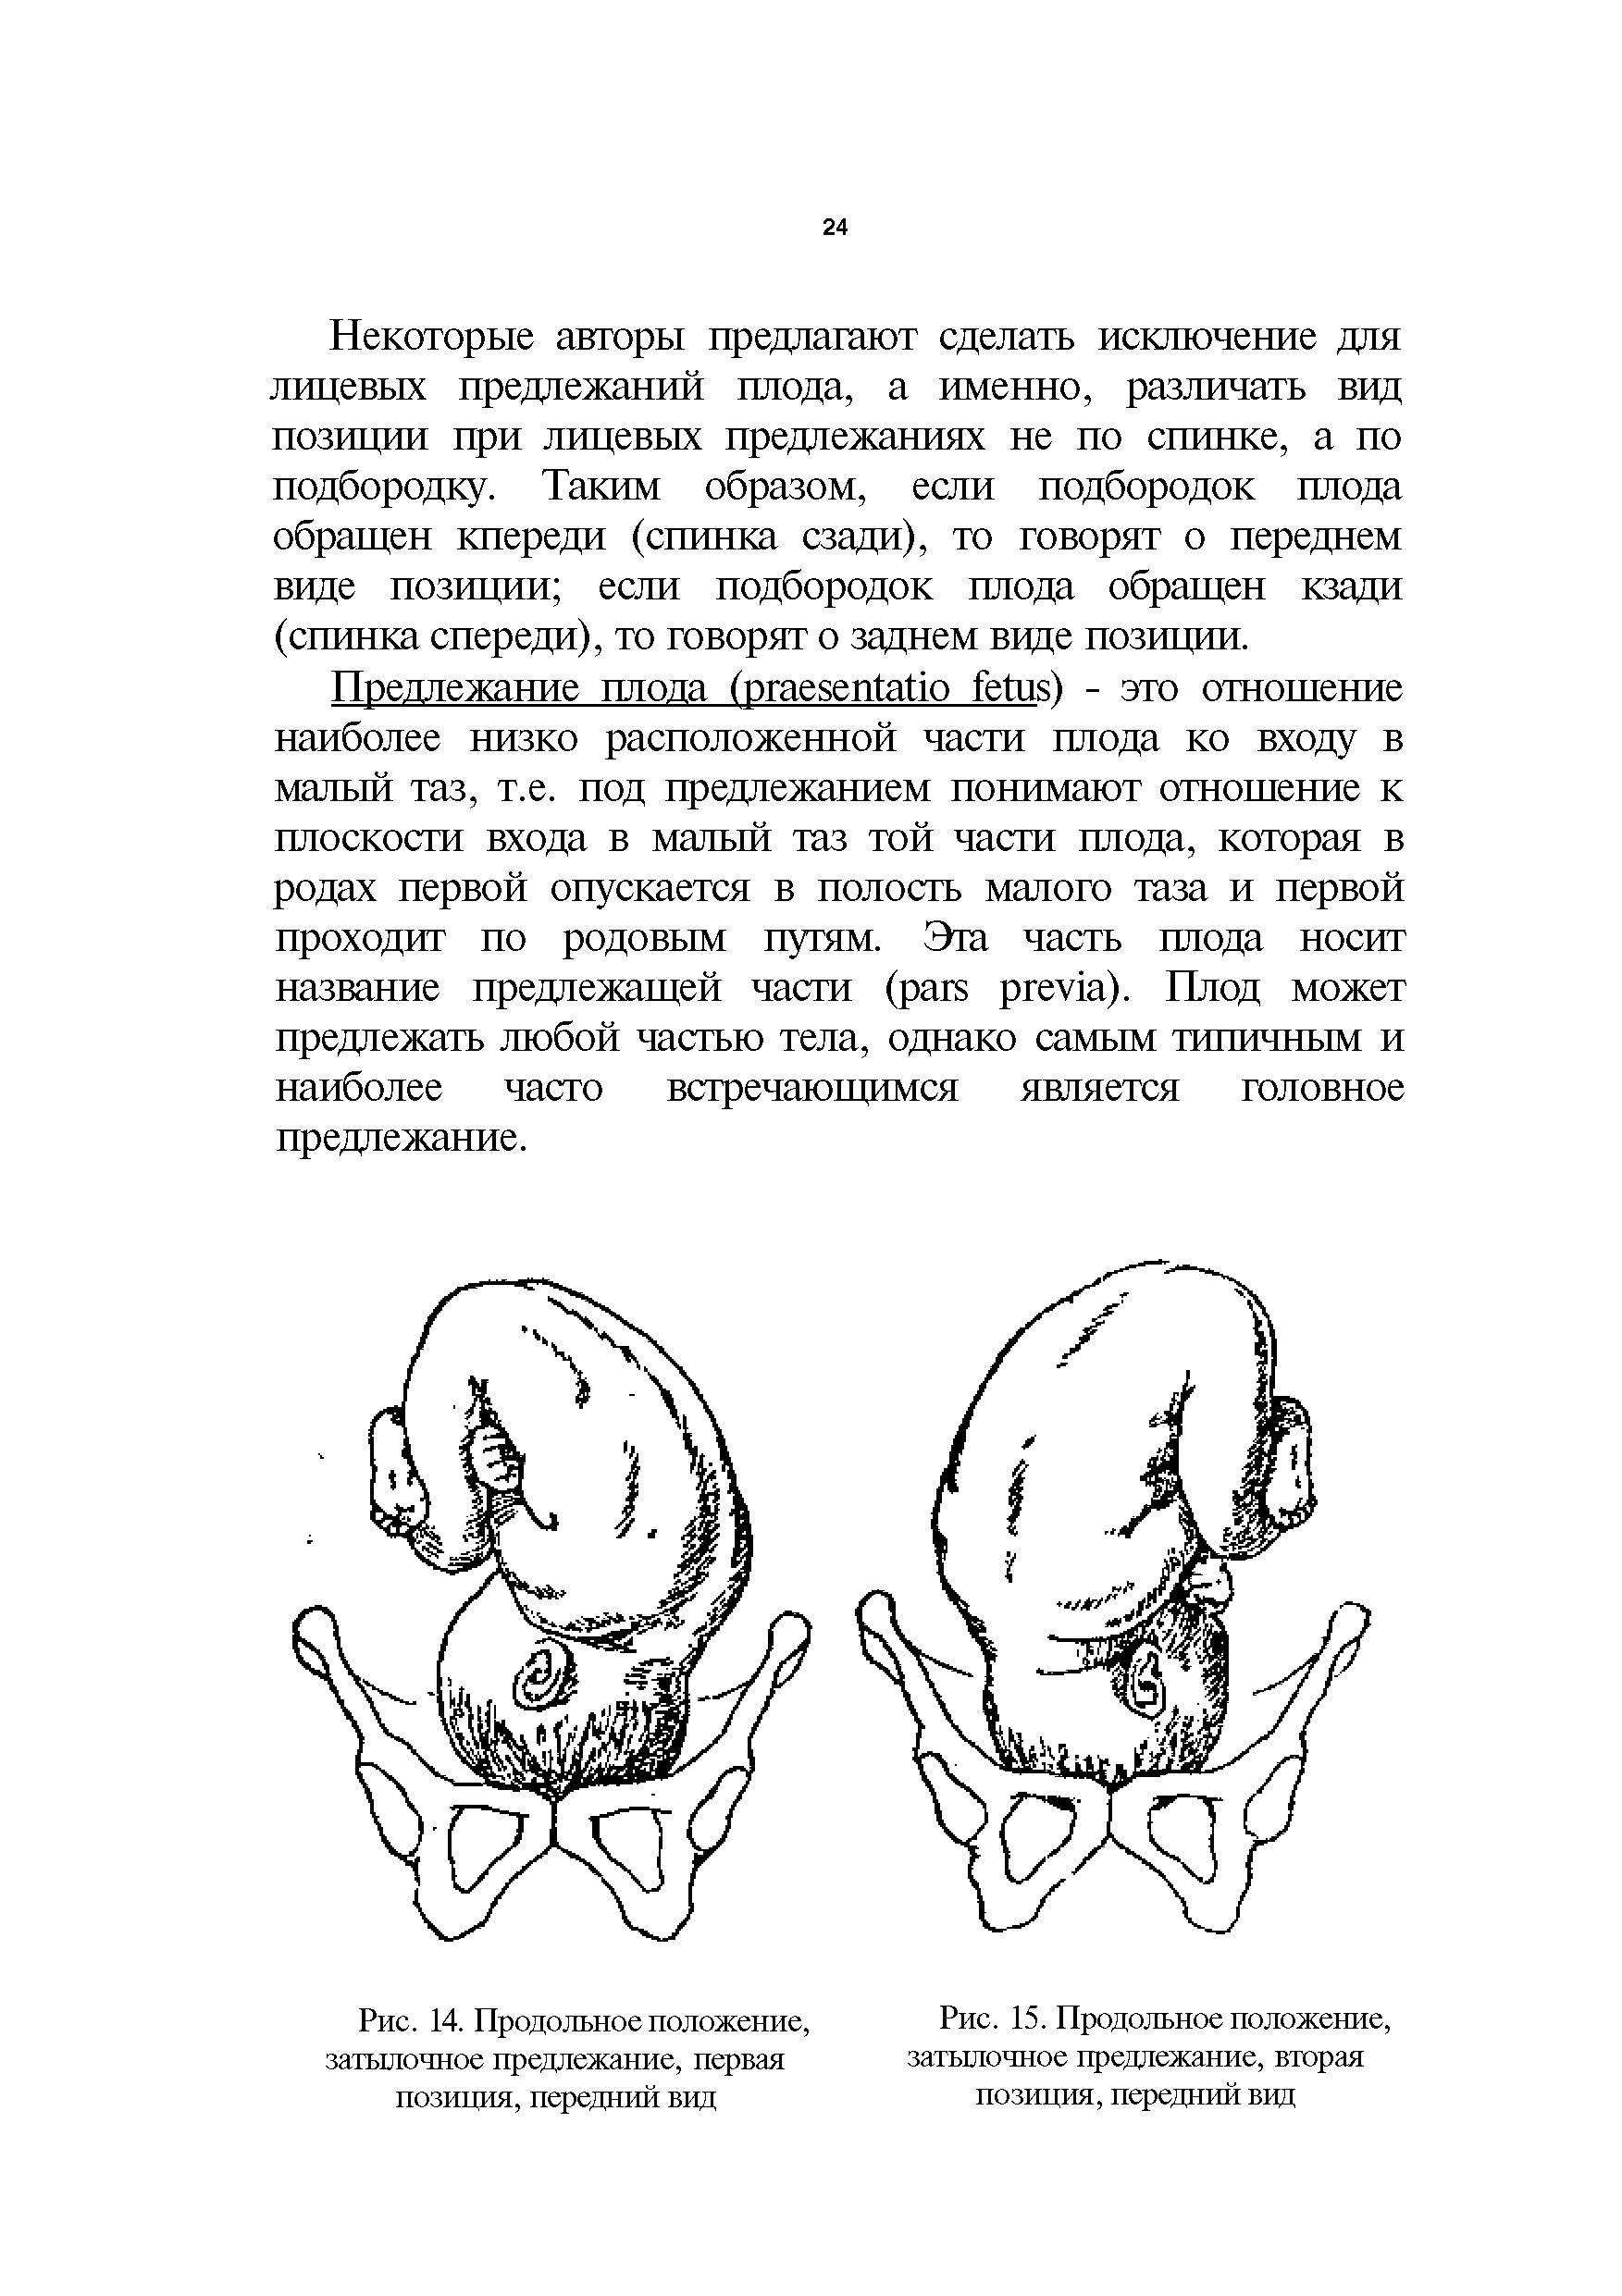

Во время беременности, положение плода имеет большое значение для мамы и малыша. Одним из типичных положений является продольное предлежание головное. В этом положении голова малыша находится внизу, а ножки - наверху. Это положение достаточно распространено и предпочтительно для естественных родов.

1 Позиция передний вид затылочного предлежания

Фото положения плода во время беременности

Ниже приведены несколько фотографий, которые помогут вам визуализировать положение плода во время беременности.